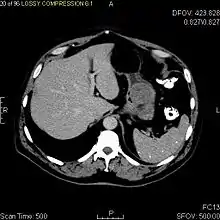

Радиологические исследования используются для уточнения локализации новообразования, выявления признаков инвазии и метастазирования. Проявления ГИСО варьируют в зависимости от размера опухоли и поражённого органа. Диаметр опухоли может составлять от нескольких миллиметров до более 30 см. Крупные опухоли обычно вызывают клинические проявления, бессимптомные опухоли обычно небольших размеров и имеют лучший прогноз.[3][16] Большие опухоли чаще ведут себя более злокачественно, однако и небольшие ГИСО могут иметь агрессивное течение.[17]

Так как ГИСО происходят из мышечного слоя (который располагается глубже слизистого и подслизистого слоёв), небольшие ГИСО чаще визуализируются как подслизистое или внутристеночное объёмное образование. При исследовании желудочно-кишечного тракта с барием обычно выявляются ровные контуры образования, формирующие прямой или тупой угол со стенкой, что наблюдается и при любых других интрамуральных процессах. Поверхность слизистой интактна, за исключением случаев изъязвления, которые присутствуют при 50 % ГИСО. При КТ с контрастным усилением, небольшие ГИСО обычно визуализируются как интрамуральные образования с ровными, чёткими контурами и гомогенным контрастированием.

По мере роста опухоли, она может проецироваться снаружи от органа (экзофитный рост) и/или в просвете органа (интралюминальный рост); чаще всего ГИСО растут экзофитно, таким образом большая часть опухоли располагается в проекции брюшной полости. Если увеличение объёма опухоли опережает рост её кровоснабжения, опухоль может некротизироваться в толще, с формированием центральной зоны жидкостной плотности и кавитацией, что может приводить к изъязвлению и формированию соустья с полостью органа. В этом случае исследование с бариевой взвесью может демонстрировать газ, уровни газ/жидкость или депонирование контрастного препарата в этих областях.[17][18] При КТ с контрастным усилением крупные ГИСО выглядят негомогенно, в связи с неоднородностью структуры опухоли, обусловленной участками некроза, кровоизлияниями и полостями, что радиологически проявляется контрастированием опухоли преимущественно по периферии.[16]

Злокачественность может проявляться локальной инвазией и метастазами, обычно в печень, сальник и брюшину. Однако встречаются случаи метастазирования в кости, плевру, лёгкие и забрюшинное пространство. По сравнению с аденокарциномой желудка или лимфомой желудка/тонкой кишки, злокачественная лимфаденопатия при ГИСО не типична (<10 %).[16] При отсутствии метастазов радиологическими признаками злокачественности являются большие размеры опухоли (>5 cm), гетерогенное контрастирование после введения контрастного препарата и наличие изъязвлений.[3][16][22] Также явно злокачественное поведение (без учёта опухолей со злокачественным потенциалом) реже наблюдается при ГИСО желудка, с отношением доброкачественных опухолей к явно злокачественным 3-5:1.[3] Даже в случае наличия радиологических признаков злокачественности, следует учитывать, что они могут быть обусловлены другой опухолью; окончательный диагноз должен быть установлен иммуногистохимическим методом.

Рентгенографические исследования с барием и компьютерная томография обычно применяются для обследования пациентов с абдоминальными жалобами. Исследования с барием выявляют патологические изменения в 80 % случаев ГИСО.[17] Однако некоторые ГИСО могут располагаться полностью вне просвета органа, что делает невозможным их выявление при исследовании с барием. Даже в случае выявления патологических изменений при рентгенографии с барием, необходимо последующее дообследование методами МРТ или КТ. КТ-исследование проводится с пероральным и внутривенным контрастным усилением, и позволяет визуализировать ГИСО в 87 % случаев[17] Мягкие ткани наиболее контрастны при МРТ, что помогает в выявлении интрамуральных образований. Для оценки васкуляризации опухоли необходимо внутривенное введение контрастного препарата.

Методами выбора в диагностике ГИСО являются КТ и МРТ,[23]:20–21 и, в некоторых случаях, эндоскопическое УЗИ. Томографические методы позволяют уточнить органную принадлежность опухоли (что может быть затруднительно при её больших размерах), визуализировать инвазию в соседние органы, асцит и метастазы.